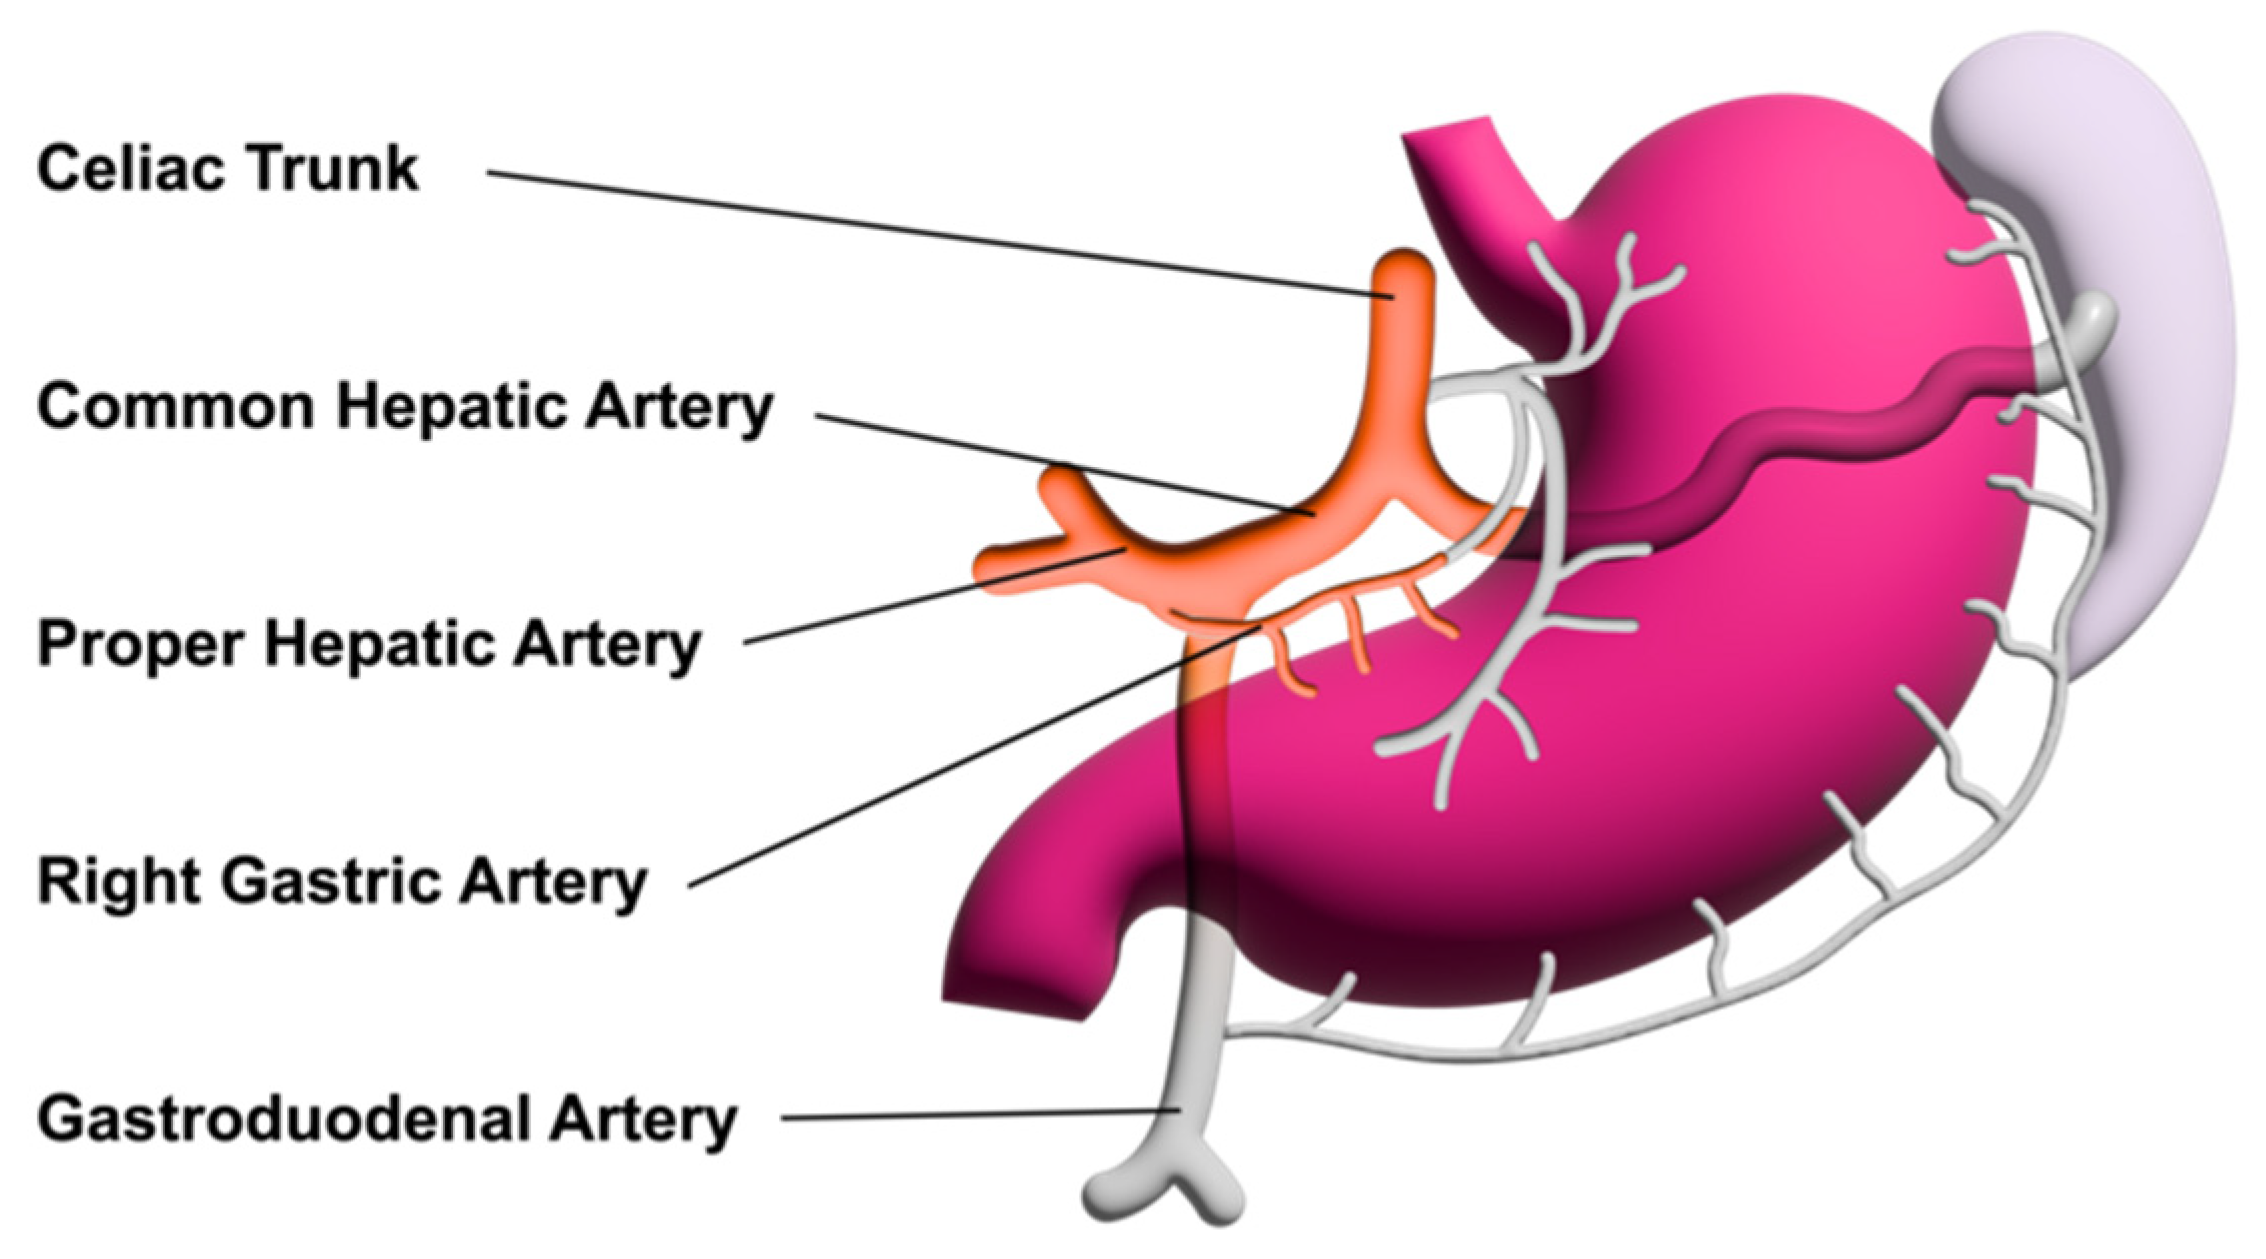

2.3.1. Determination of Vessel Diameter

2.3.2. Location of the Probe, Insonation Angle, and Doppler Window